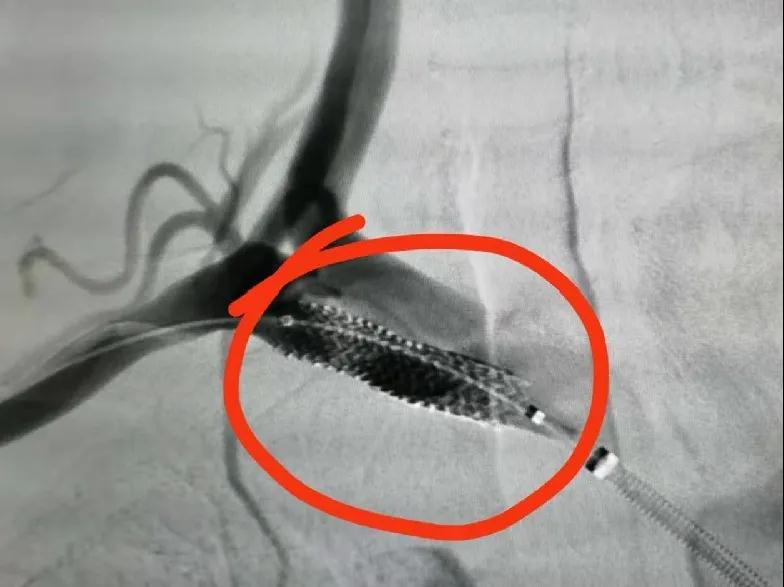

在征得王先生及家人同意后,魏主任組織介入團隊進行術前討論,依據患者病情擬定了詳細的手術方案,手術由魏主任親自操作,在手術中意想不到的遇到了重重困難:一是斑塊硬開通困難,二是斑塊脫落形成栓塞,三是病灶在夾層,四是支架不能堵塞椎動脈等,給手術帶來很大風險,憑借多年的臨床實踐,終于把血管開通、支架植入。后經造影顯示:右鎖骨下動脈支架置入后恢復前向血流,不再盜血,手術歷時4個小時,整個過程可謂“驚心動魄”。

支架植入后